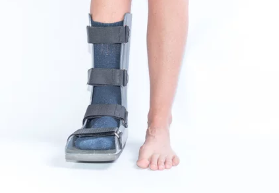

- 복합 골절: 뼈가 여러 조각으로 나뉘거나, 관절에 영향을 미치는 경우에는 6주에서 8주 이상이 걸릴 수 있습니다. 이 경우 물리치료와 보조기구 사용이 필요할 수 있습니다.

- 신발 선택: 회복 중에는 단단한 밑창이 있는 신발을 신어 발가락을 보호하고, 충격 흡수가 되는 신발을 착용하는 것이 좋습니다.